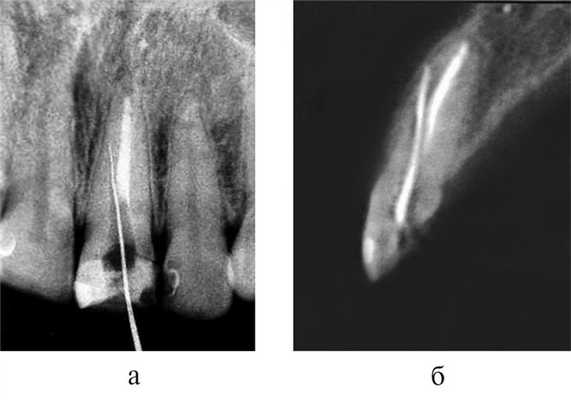

Обтурированный перфорационный канал в боковых стенках корней зубов на внутриротовых периапикальных рентгенограммах выявлялся только при правильно выбранной проекции съемки (рис. 5, а, б). При перфорации вестибулярной или язычной (небной) стенок корней зубов тень пломбировочного материала или эндодонтического инструмента находилась в пределах контуров корня, что не позволяло составить объективное представление о наличии перфорации (рис. 6, а, б).

Рис. 5. Отображение перфорации корня зуба 1.2 в зависимости от проекции съемки. а — на внутриротовой периапикальной рентгенограмме тень пломбировочного материала видна в пределах корня зуба; б — на периапикальной рентгенограмме в косой проекции — картина перфорации корня зуба.

Рис. 6. Исследование зуба 2.1. а — на внутриротовой периапикальной рентгенограмме тень концевого отдела корневой иглы отображается в проекции корня зуба; б — на косом срезе КЛКТ определяется перфорация вестибулярной стенки корня зуба.